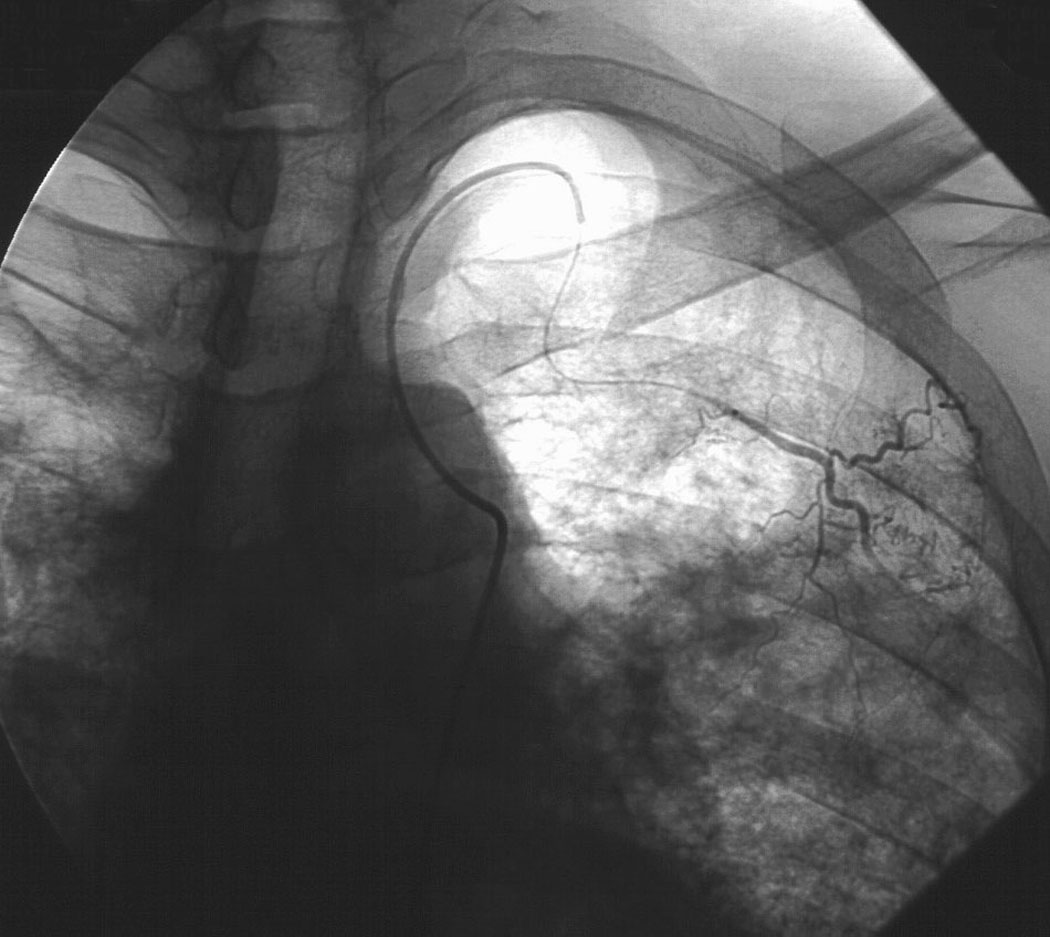

Хирургические процессы при эмболизации гемангиомы на фото

Раздел: Снимки-откровения